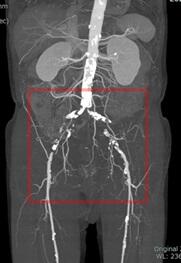

当院で血管内治療を行った閉塞性動脈硬化症の一例